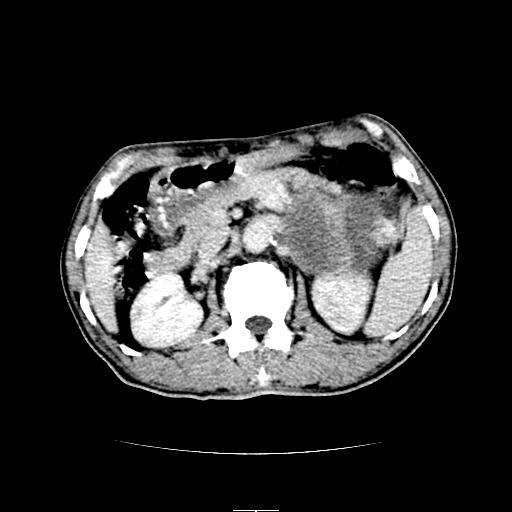

左上腹胃、脾及胰腺间巨大囊性占位性病变,内见多数薄隔,有轻度强化,明显占位效应。左肾见一小囊肿。

考虑:1、左上腹巨大囊肿(可能来源于胰腺)。

2、左肾小囊肿。

左上腹胃、脾及胰腺间巨大囊性占位性病变,内见多数薄隔,有轻度强化,明显占位效应,胰腺及左肾结构清楚,明显向后下方推压 移位。左肾见一小囊肿.多考虑:1 网膜巨大囊肿。2 左肾小囊肿。

1胃脾胰之间一巨大囊性影,胃明显向前推移,胰体尾部似肥大,考虑囊性影来源于胰腺(假性囊肿?)2左肾小囊肿。

左上腹囊性占位,与胰腺分界不清,考虑起源于胰腺可能。

左上腹囊性占位,虽与胰腺分界不清,胰尾似乎受压前移,病灶最大截面并不在胰腺水平,考虑来源于网膜可能性大吧,应再详细追问病史.

左上腹胃、脾及胰腺间巨大囊性占位性病变,其内见多数薄隔,有轻度强化,明显占位效应。左肾见一小囊性变。

左肾囊肿;网膜巨大囊肿。